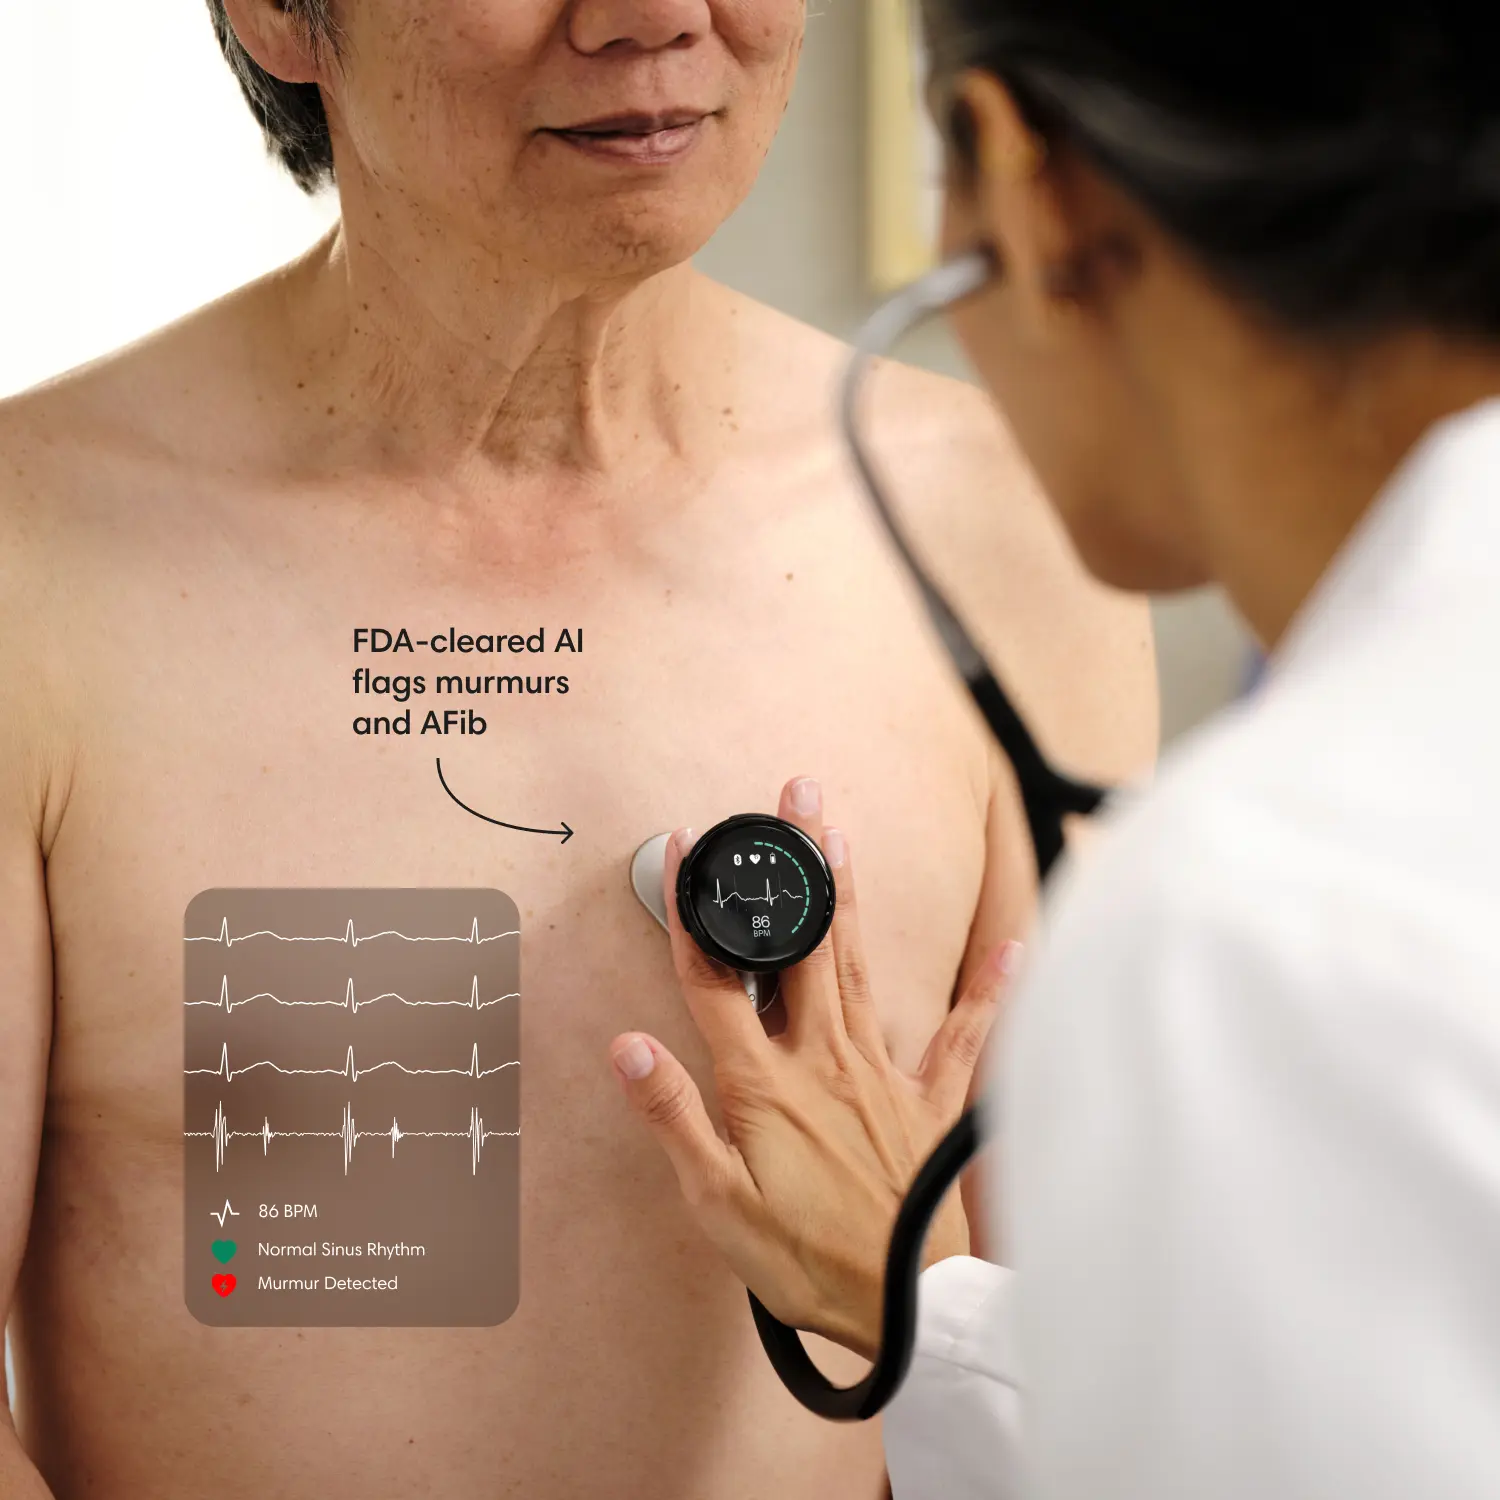

Enhance expertise with AI.

Eko’s FDA-cleared AI flags murmurs and other abnormalities in seconds, leading to earlier heart and lung disease detection and better patient care.

Eko analysis software, or Eko AI, is FDA-cleared software that includes screening algorithms to assist clinicians in detecting suspected abnormalities.

When the Eko App is paired with a compatible digital stethoscope, Eko AI automatically checks for murmurs and/or AFib. To receive AI results, you must take a recording with the stethoscope or the Eko App. (The CORE 500™ Digital Stethoscope is required for AFib detection.)

The Eko App summarizes any findings, including potential murmurs, AFib, or other abnormalities detected. These findings aren’t a diagnosis, but are intended to aid the clinician in reaching a diagnosis accurately, quickly, and confidently.